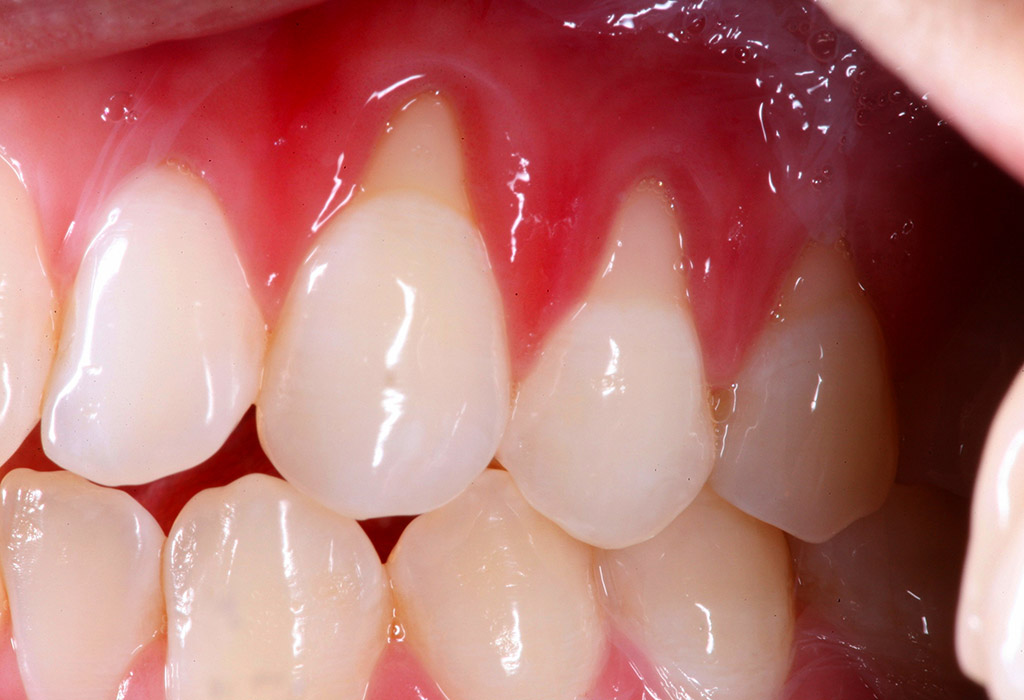

Las encías retraídas son un problema frecuente que ocurre cuando el tejido gingival se desplaza hacia abajo, dejando expuesta la raíz del diente. Esta situación puede provocar sensibilidad dental, mayor riesgo de caries radiculares y afectar la estética de la sonrisa.

La recesión gingival es la pérdida progresiva del tejido de la encía que protege el cuello y la raíz del diente. Puede aparecer en un solo diente o afectar varias zonas de la boca.

✔ Sensibilidad dental

✔ Raíz del diente visible

✔ Encías más finas o retraídas

✔ Dientes que parecen más largos

✔ Sangrado o inflamación gingival